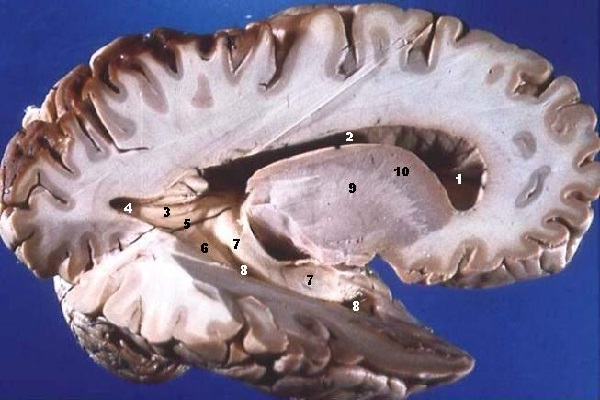

Estructura

La sustancia blanca se ubica principalmente en la médula espinal y está compuesta por una gran cantidad de fibras nerviosas conocidas como neuroglias.

Si se realiza un corte transversal en la sustancia blanca, se observa que está cubierta por una capa de sustancia gris.

– Cordones de la sustancia blanca

La sustancia blanca está conformada por tres cordones diferentes. La diferenciación de cada uno de estos cordones se realiza a través de su localización en la médula espinal.

a) Cordón anterior

El cordón anterior se ubica entre la fisura mediana ventral y los surcos ventrolaterales de la medula espinal. Se caracteriza por contener tractos motores que controlan los movimientos asociados a los movimientos voluntarios.

b) Cordón lateral

El cordón lateral se halla entre los surcos ventrolaterales y los surcos dorsolaterales. Este contiene fascículos relacionados con los movimientos voluntarios, el tracto corticoespinal lateral y fascículos relacionados con la sensibilidad.

c) Cordón posterior

Finalmente, el tercer y último cordón de la sustancia blanca se ubica entre el surco mediano dorsal y los surcos dorsolaterales.

El cordón posterior se caracteriza por quedar subdividido en dos fascículos en la región cervical y torácica alta, gracias a la presencia del surco intermedio dorsal.

Los dos fascículos que contiene el cordón posterior son el fascículo de grácil (en la región medial) y el fascículo cueniforme (en la región lateral). Ambos fascículos contienen fibras ascendentes pertenecientes al tracto epicrítico, propiocepción consciente y sensibilidad vibratoria.

Tractos del cerebro

La sustancia blanca se organiza en forma de conjuntos de fibras nerviosas. Esta organización se observa tanto dentro como fuera del sistema nervioso central.

Los tractos del cerebro son pues un conjunto de fibras nerviosas de proyección que envían información procesada por la materia gris a las diferentes regiones del organismo situadas fuera del encéfalo.

Otro tipo de fibras de sustancia blanca son las fibras de asociación, las cuales conectan diferentes regiones cerebrales del mismo hemisferio.

Finalmente, el tercer y último tipo corresponde a las comisuras interhemisféricas, las cuales contienen estructuras de diferentes hemisferios cerebrales.

Además, a parte de la médula espinal, el cerebro se caracteriza por presentar una gran cantidad de estructuras que están principalmente constituidas por sustancia blanca. La más importante es el cuerpo calloso, una comisura interhemisférica que conecta los dos hemisferios del cerebro.